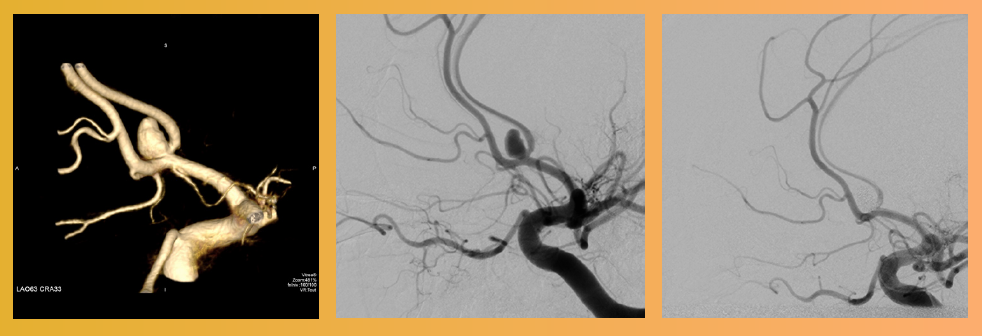

L’accident vasculaire cérébral hémorragique peut se présenter sous plusieurs formes cliniques. La plus spectaculaire et la plus complexe est l’hémorragie sous arachnoïdienne secondaire à une rupture d’anévrisme. Cette affection redoutable, associée à une haute mortalité (43 % en Europe) et morbidité, est sous diagnostiquée. Elle est en effet responsable d’un pourcentage non négligeable des morts dites «subites». Un diagnostic précoce est décisif, et permet d’orienter le patient vers un centre à haut volume de recrutement et de traitement. Au CHR Liège, les services de neuroradiologie et de neurochirurgie effectuent chaque année en collaboration plus de 75 procédures.

• Phase initiale : intervention urgente concertée entre les neuroradiologues et les neurochirurgiens pour exclure l’anévrisme tout en assurant l’homéostasie cérébrale mise en péril par l’hypoxie cérébrale contemporaine du saignement, le déclenchement d’une cascade neuroinflammatoire secondaire, la menace d’une hydrocéphalie par altération de la résorption du LCR et l’atteinte d’autres fonctions vitales. Les altérations de la fonction cardiaque et respiratoire secondaires à des phénomènes neurohumoraux imparfaitement compris sont fréquentes.